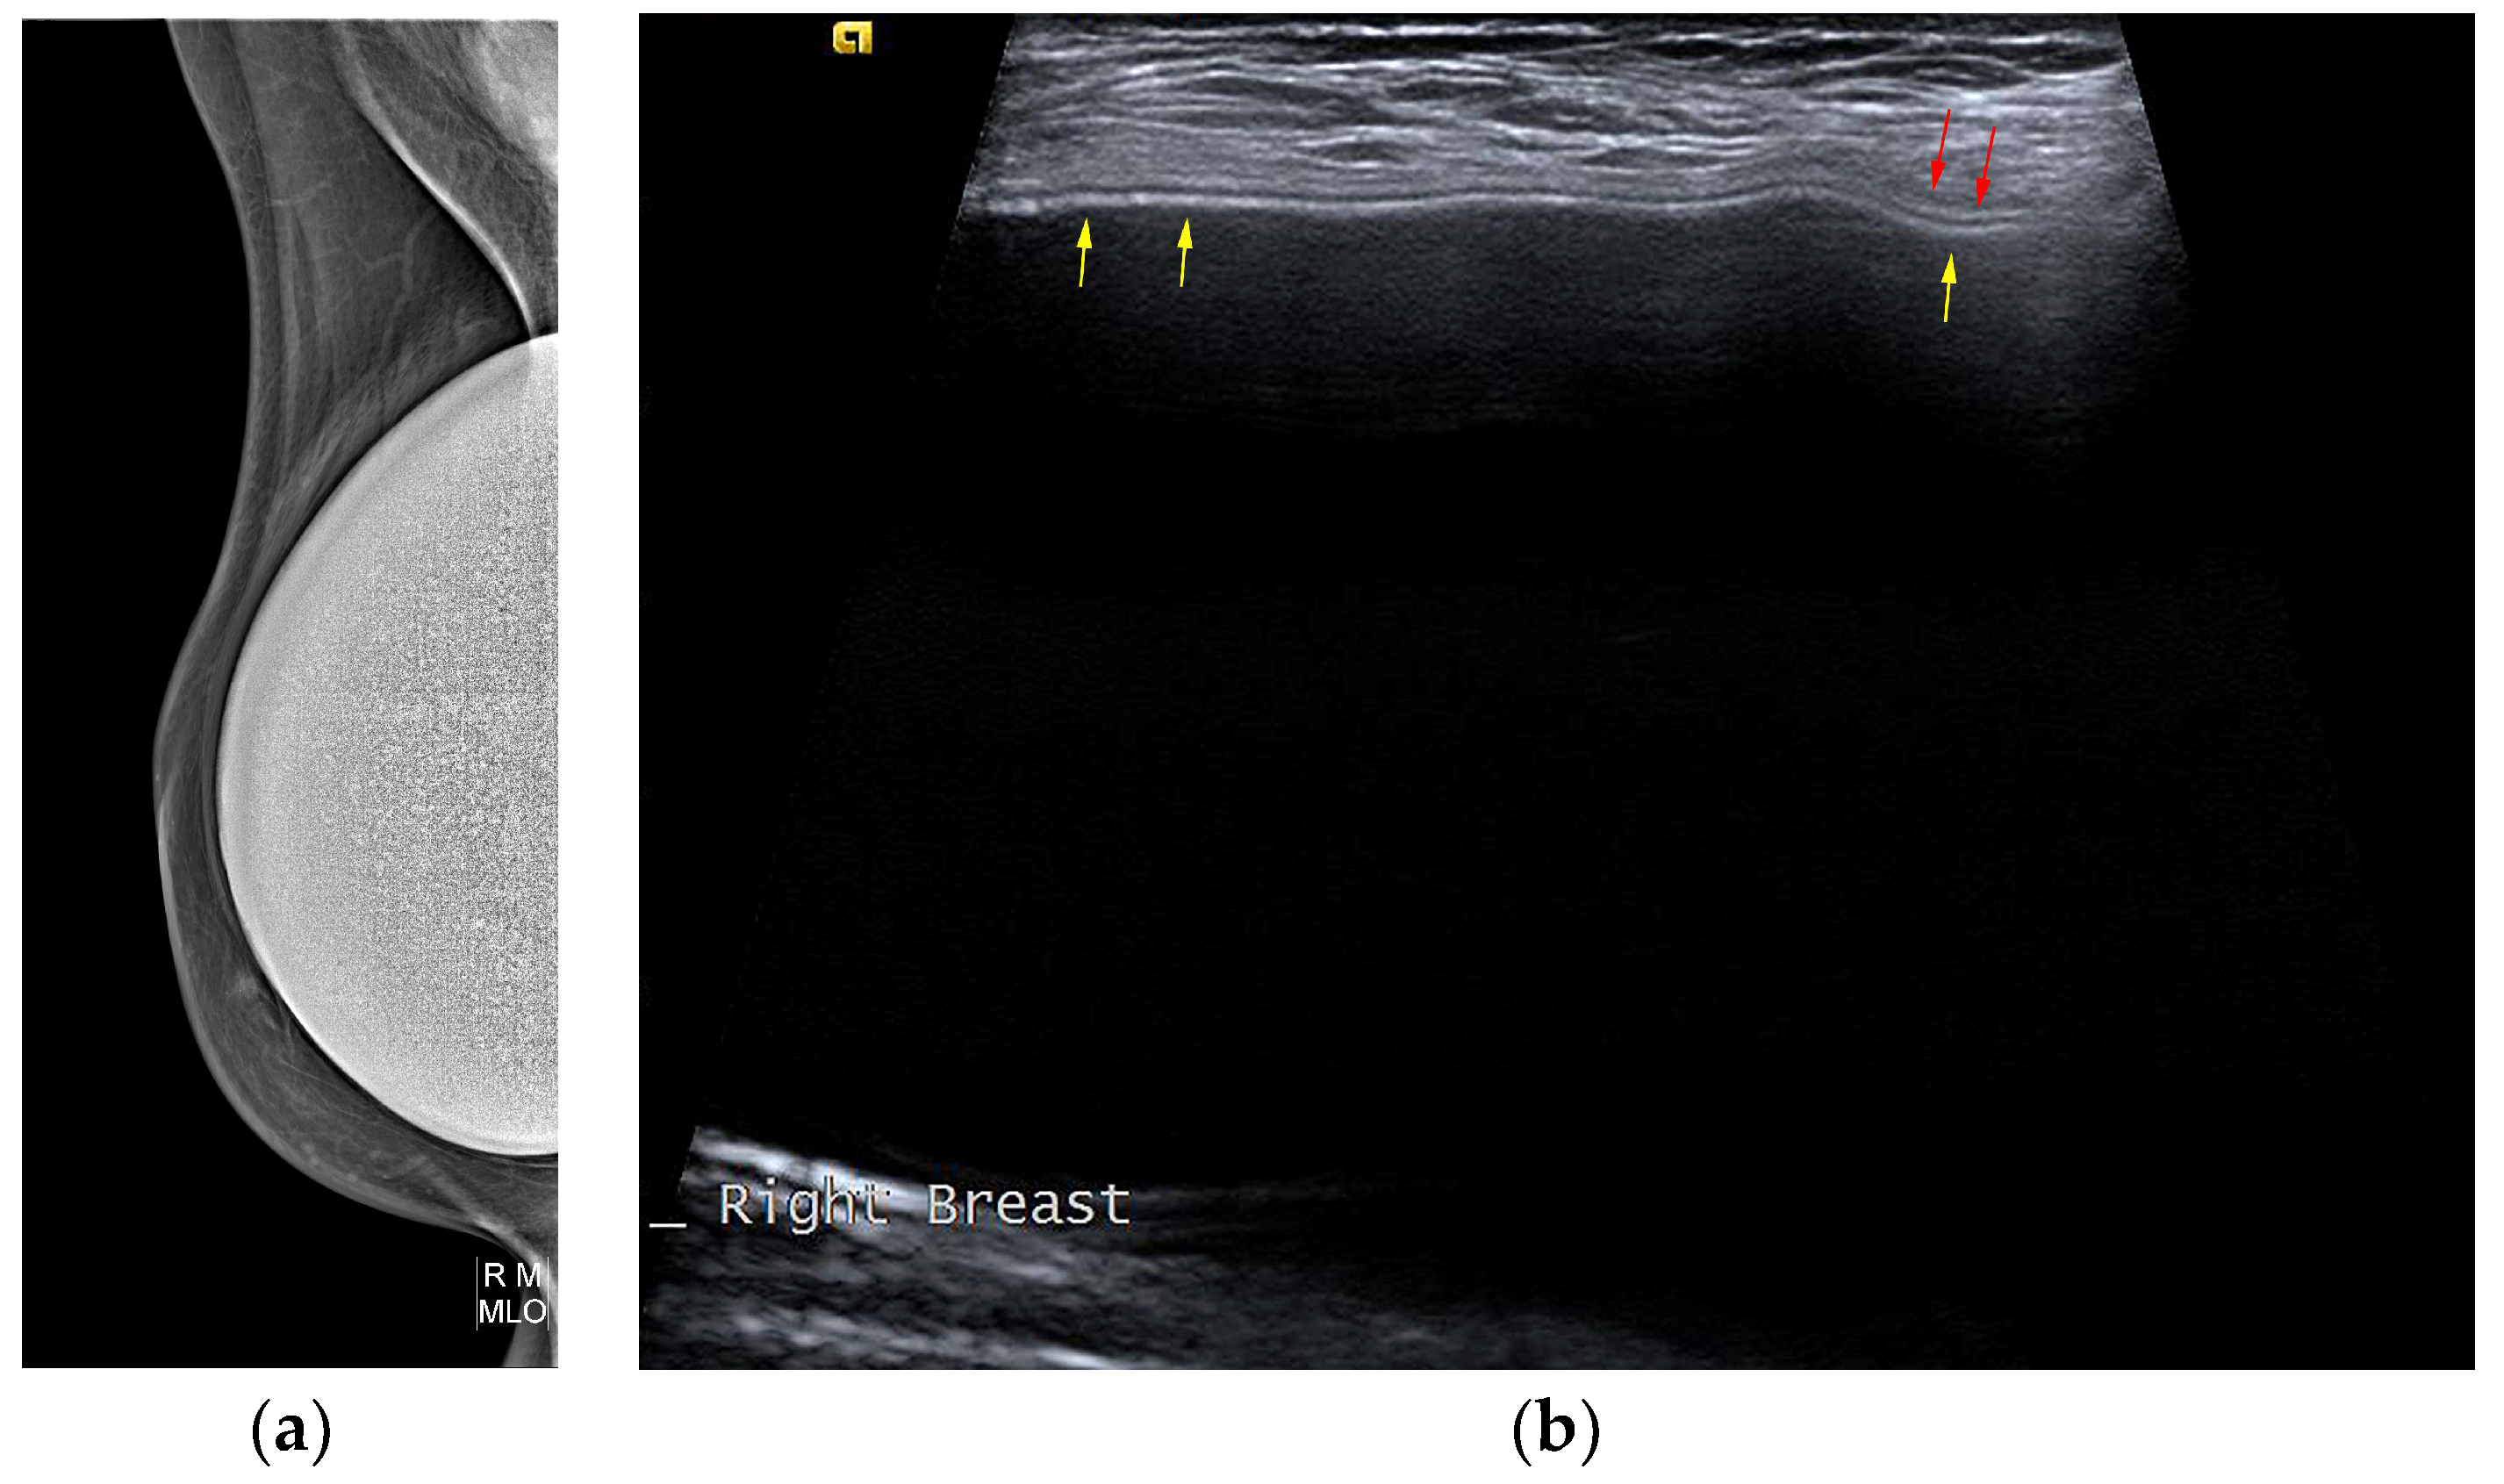

5.2.5. Implant Rupture

- Venkataraman, S.; Hines, N.; Slanetz, P.J. Challenges in mammography: Part 2, multimodality review of breast augmentation—Imaging findings and complications. Am. J. Roentgenol. 2011, 197, W1031–W1045. [Google Scholar] [CrossRef] [PubMed]

- Wong, T.; Lo, L.W.; Fung, P.Y.; Lai, H.Y.; She, H.L.; Ng, W.K.; Kwok, K.M.; Lee, C.M. Magnetic resonance imaging of breast augmentation: A pictorial review. Insights Imaging 2016, 7, 399–410. [Google Scholar] [CrossRef] [PubMed]

- Norena-Rengifo, B.D.; Sanin-Ramirez, M.P.; Adrada, B.E.; Luengas, A.B.; Martinez de Vega, V.; Guirguis, M.S.; Saldarriaga-Uribe, C. MRI for Evaluation of Complications of Breast Augmentation. Radiographics 2022, 42, 929–946. [Google Scholar] [CrossRef]

- Seiler, S.J.; Sharma, P.B.; Hayes, J.C.; Ganti, R.; Mootz, A.R.; Eads, E.D.; Teotia, S.S.; Evans, W.P. Multimodality Imaging-based Evaluation of Single-Lumen Silicone Breast Implants for Rupture. Radiographics 2017, 37, 366–382. [Google Scholar] [CrossRef] [PubMed]

- Ahn, C.Y.; DeBruhl, N.D.; Gorczyca, D.P.; Shaw, W.W.; Bassett, L.W. Comparative silicone breast implant evaluation using mammography, sonography, and magnetic resonance imaging: Experience with 59 implants. Plast. Reconstr. Surg. 1994, 94, 620–627. [Google Scholar] [CrossRef] [PubMed]

- Ikeda, D.M.; Borofsky, H.B.; Herfkens, R.J.; Sawyer-Glover, A.M.; Birdwell, R.L.; Glover, G.H. Silicone breast implant rupture: Pitfalls of magnetic resonance imaging and relative efficacies of magnetic resonance, mammography, and ultrasound. Plast. Reconstr. Surg. 1999, 104, 2054–2062. [Google Scholar] [CrossRef] [PubMed]

- O’Toole, M.; Caskey, C.I. Imaging spectrum of breast implant complications: Mammography, ultrasound, and magnetic resonance imaging. Semin. Ultrasound CT MRI 2000, 21, 351–361. [Google Scholar] [CrossRef] [PubMed]

- Salzman, M.J. Silent Rupture of Silicone Gel Breast Implants: High-Resolution Ultrasound Scans and Surveys of 584 Women. Plast. Reconstr. Surg. 2022, 149, 7–14. [Google Scholar] [CrossRef]

- Goldammer, F.; Pinsolle, V.; Dissaux, C.; Pelissier, P. Accuracy of mammography, sonography and magnetic resonance imaging for detecting silicone breast implant ruptures: A retrospective observational study of 367 cases. Ann. Chir. Plast. Esthet. 2021, 66, 25–41. [Google Scholar] [CrossRef]

- Rochira, D.; Cavalcanti, P.; Ottaviani, A.; Tambasco, D. Longitudinal Ultrasound Study of Breast Implant Rupture Over a Six-Year Interval. Ann. Plast. Surg. 2016, 76, 150–154. [Google Scholar] [CrossRef]